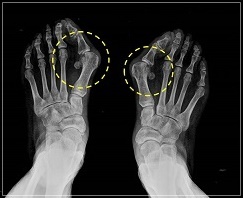

무지외반증 여부의 진단은 시진과 촉진(발가락 모양, 굳은살 등)으로 가능하지만 치료 방침을 결정하기 위해서는 방사선 검사가 필요합니다. 뼈와 뼈가 이루는 각도, 관절의 변형과 염증, 운동 범위 등을 측정합니다.